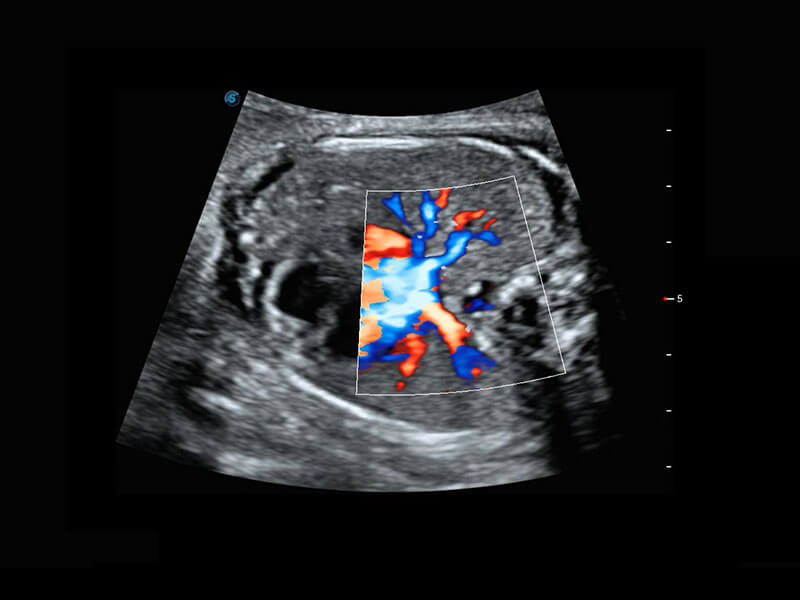

胎儿体循环

P60搭载一系列胎儿心脏成像技术,实现精细的胎儿心脏评估。